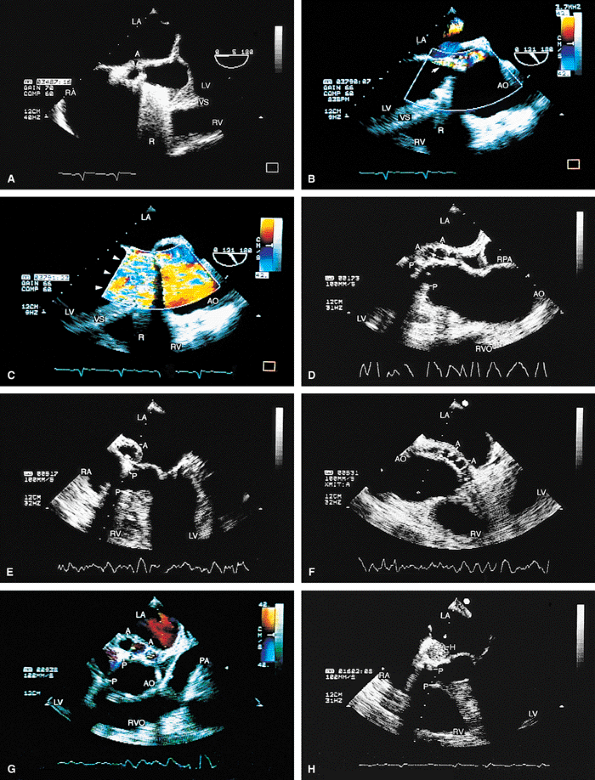

FIGURE 5.14. Mitral annuloplasty ring. The ring (R) is seen in diastole in A and in systole in B. C. Color Doppler examination shows moderate residual mitral regurgitation (MR) in this patient, who had severe MR before ring placement. D. A systolic frame shows ring (R) echoes in another patient following mitral annuloplasty. LA, left atrium; LV, left ventricle; MV, mitral valve; PA, pulmonary artery; RV, right ventricle; RVO, right ventricular outflow tract. |